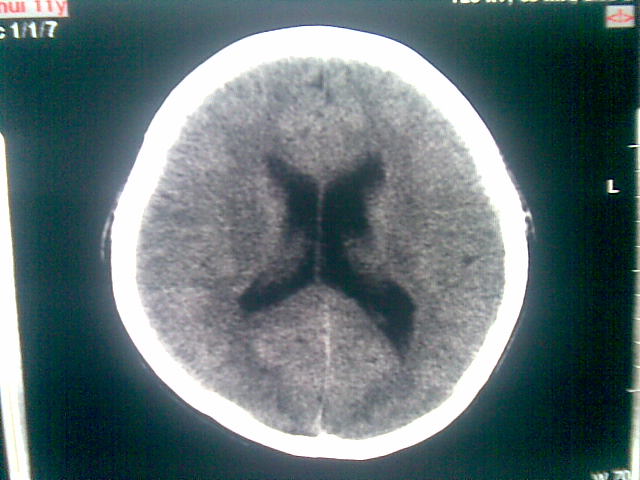

以下是引用随光逐影在2010-1-5 16:32:00的发言:[br]1)鞍上池囊性占位性病变,不排除蛛网膜囊肿可能;建议行mri检查。2)脑积水。

以下是引用yangyang2000在2010-1-5 20:41:00的发言:[br])鞍上池囊性占位性病变,不排除蛛网膜囊肿可能;建议行mri检查。2)脑积水

以下是引用yangyudong333在2010-1-5 21:28:00的发言:[br]1)鞍上池囊性占位性病变,不排除蛛网膜囊肿可能;建议行mri检查。2)脑积水。